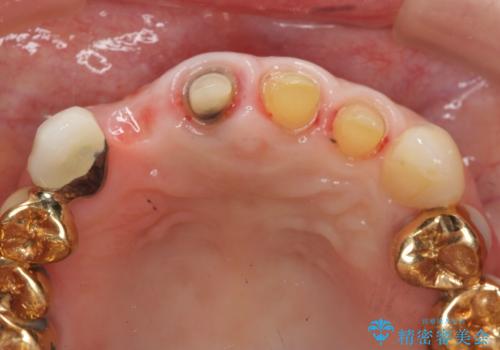

再根管治療を行うべくクラウン除去を行ったところ、右上側切歯に保存不可能な垂直性の破折が認められたため抜去が必要になりました。

即切歯の抜歯を行う場合犬歯を含めたブリッジによる補綴計画を立てることが多いですが、今回は犬歯から大臼歯にかかる大きなブリッジが既に装着されていたため予算とご希望を相談し前歯のみの延長ブリッジ補綴で治療を行っていくこととしました。

- 54万円(仮歯・感染根管治療・ファイバーコア・ジルコニアクラウン×4) (税別)費用は治療当時の料金となります